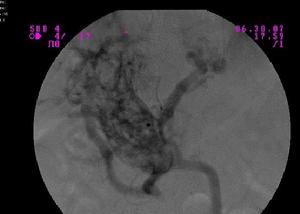

4、腹腔穿刺,腹水病人必須行診斷性腹腔穿刺,腹水為滲出性,內含大量嗜酸性粒細胞,必須做腹水塗片染色,以區別嗜酸性粒細胞和中性粒細胞。

5、腹腔鏡檢查,腹腔鏡下缺乏特異性表現,輕者僅有腹膜充血,重者可類似於腹膜轉移癌。腹腔鏡檢查的意義在於進行腹腔黏膜組織活檢,得到病理診斷。